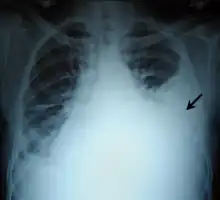

Massive left-sided pleural effusion (whiteness) in a patient presenting with lung cancer.

Massive pleural effusion, later proven to be hemothorax in a South Indian male.